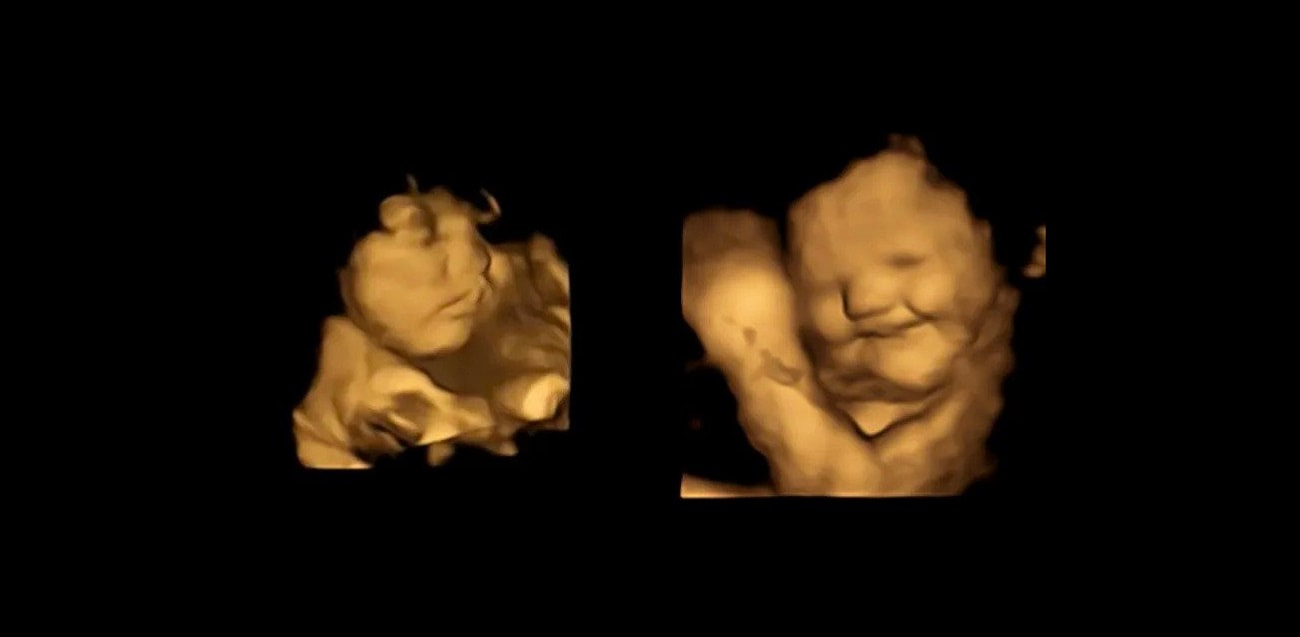

Członkowie zespołu zajmującego się tą sprawą przeprowadzili skany ultradźwiękowe w 4D, za sprawą których zaobserwowali, jak dziecko uśmiecha się, gdy jego matka je marchewkę, by wykazać się grymasem po kontakcie z jarmużem.

Uczestniczki miały od 18 do 40 lat i zostały poddane badaniu ultrasonograficznemu 4D w 32., a następnie w 36. tygodniu ciąży. Na 20 minut przed każdym wykonanym skanowaniem ciężarnym podawano tabletkę zawierającą 400mg sproszkowanej marchewki lub 400mg sproszkowanego jarmużu. Jednocześnie miały nie spożywać innych pokarmów lub napojów, które mogłyby wpłynąć na reakcje ich dzieci.

Płody reagowały na marchewkę z uśmiechem, lecz grymasiły się po kontakcie z jarmużem

W grupie kontrolnej nie podawano natomiast żadnej ze wspomnianych kapsułek. W przypadku marchewki płody miały tendencję do uśmiechania się, jednak spożycie kapsułki z jarmużem prowadziło do pojawiania się u nich grymasów. Pokazuje to, jak ogromny jest wpływ zachowań matek na ich potomstwo. Wyniki badania mają też istotne implikacje w kontekście rozwoju receptorów smaku i zapachu oraz związanej z nimi percepcji i pamięci.